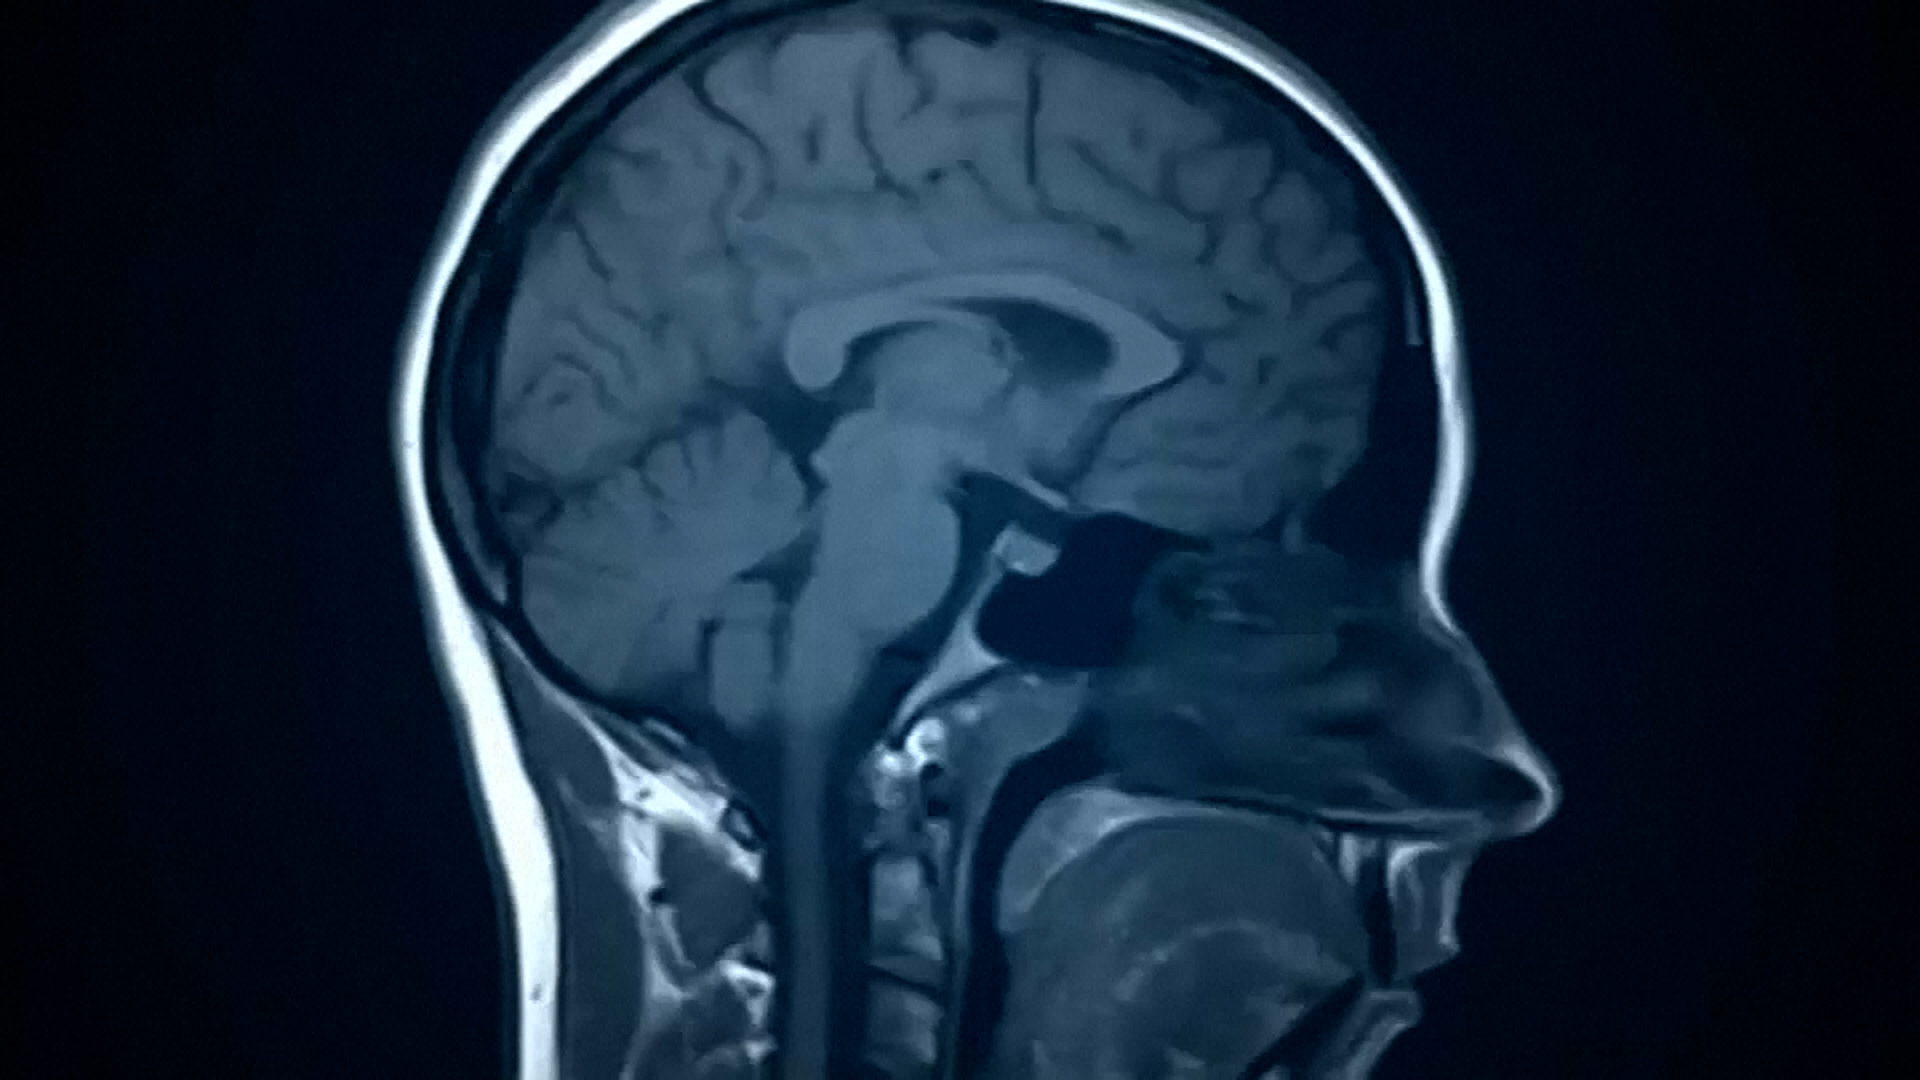

Music Listening Linked to Lower Dementia Risk, Study Finds